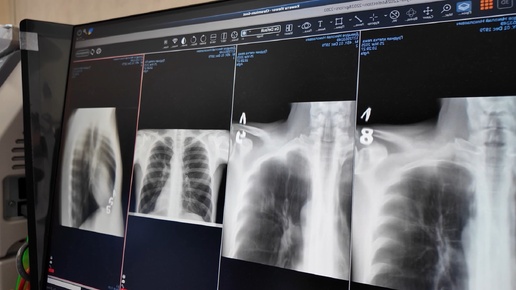

Златоуст присоединился к Всемирному Дню борьбы с туберкулезом